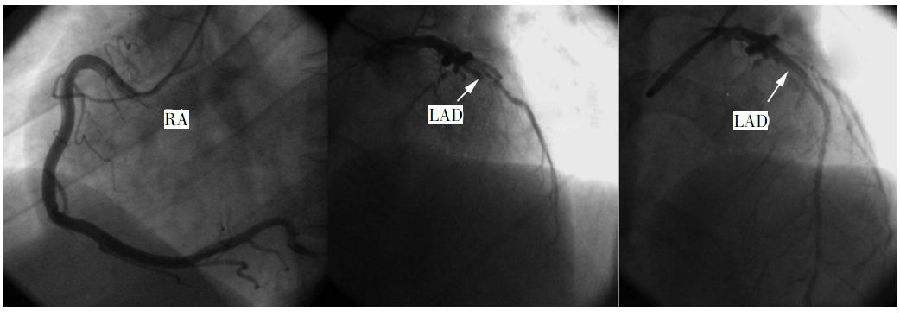

四大胸痛杀手